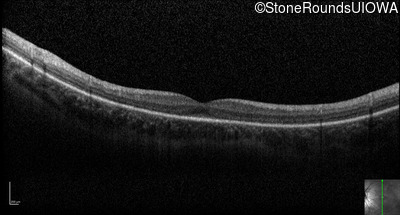

Optical Coherence Tomography - Right - 20/50

Exemplar